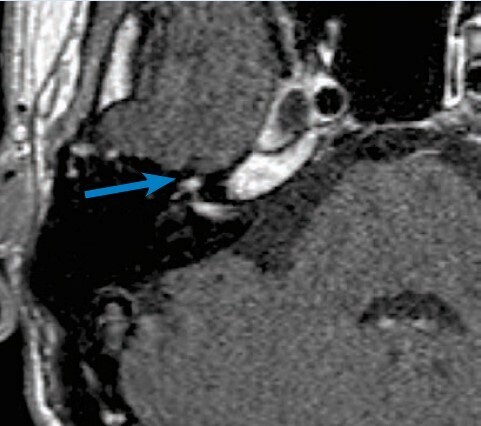

Nécessaire et utile, une audiométrie avec tympanométrie et étude des réflexes stapédiens est précieuse. Depuis les dernières recommandations de la Société française d’ORL (SFORL),6 une IRM injectée (sans urgence) est aussi préconisée. Les formes virales se caractérisent par une prise de contraste importante et focalisée du ganglion géniculé et des portions avoisinantes du nerf facial (fig. 3). Le scanner n’est indiqué qu’en cas d’otoscopie anormale, à la recherche d’une pathologie de l’oreille moyenne ou du rocher.